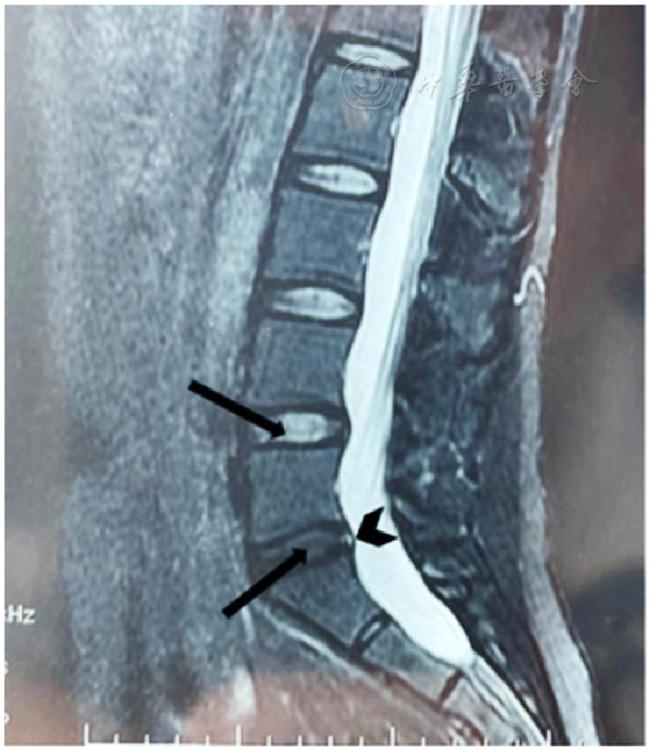

患者,女,36岁,因"腰骶部疼痛,伴持续性生理刺激反应"于2021年9月至青岛大学附属海慈医院康复科就诊。患者约6个月前从长时间蹲位劳动起身后出现腰骶部疼痛,遂入当地医院骨科就诊,查腰椎磁共振成像(MRI)示L4/L5和L5/S1椎间盘突出,伴有L5/S1椎间盘后缘高密度灶,见图1。初诊为椎间盘突出症(L4/L5、L5/S1)和盘缘性腰痛,嘱卧床休息并给予草木犀流浸液片(消脱止-M)和双氯芬酸钠双释放肠溶胶囊(戴芬)口服。因患者症状缓解不明显,多次复诊后考虑为梨状肌综合征,加用局部针灸、理疗和按摩。患者症状持续加重,并出现阵发性会阴部刺激感和双下肢抽搐、无力,骨科医师遂先后建议去神经内外科、妇科和心理科诊疗,效果不佳。患者在1次推拿按摩后自感会阴部刺激症状由阵发性变为持续性,为求进一步治疗遂来康复科就诊。

图1 病例椎间盘磁共振成像检查结果注:箭头示L4/L5和L5/S1椎间盘轻度突出,燕尾箭头示L5/S1椎间盘后部高信号区(HIZ) Figure 1 MRI results of the intervertebral discs |